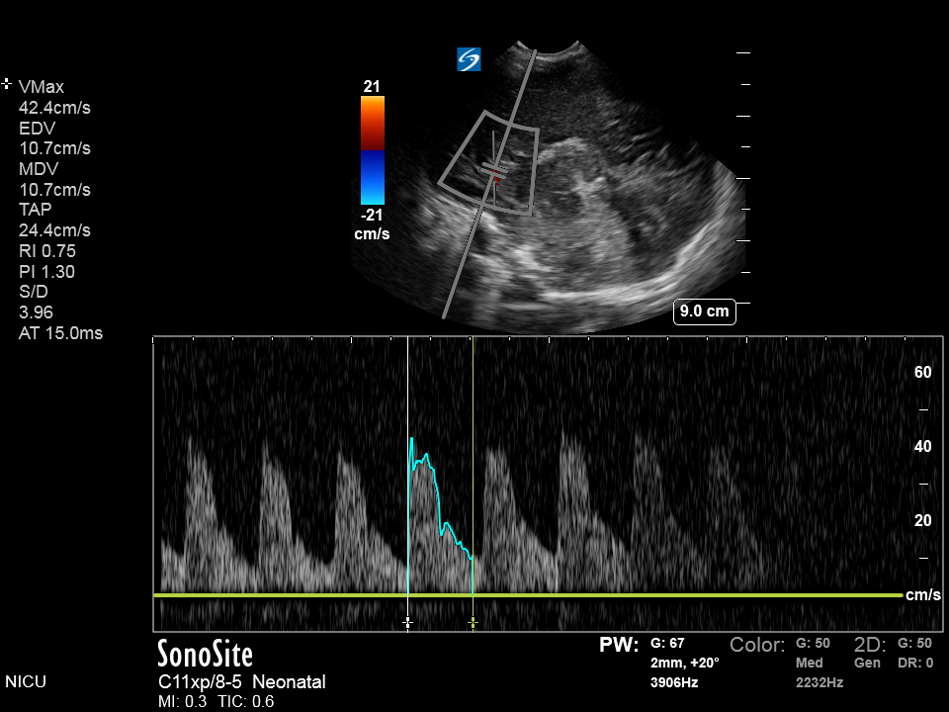

Neonatology Resistive Index 1 Image